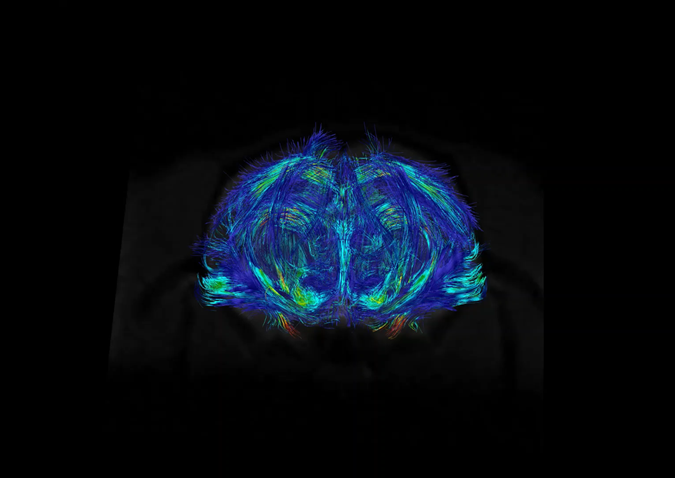

• Difüzyon tensör görüntüleme (DTI), traktografi

Dokulardaki (örneğin beyin, karaciğer) difüzyon özellikleri difüzyon ağırlıklı görüntüleme sekansları ile değerlendirilebilmektedir. Buna ek olarak, beyindeki beyaz cevher yolaklarının fraksiyonel anizotropi (FA) gibi ayrıntılı özelliklerini değerlendirmeye ve traktografisine olanak tanıyan difüzyon tensor görüntüleme yapılabilmektedir.